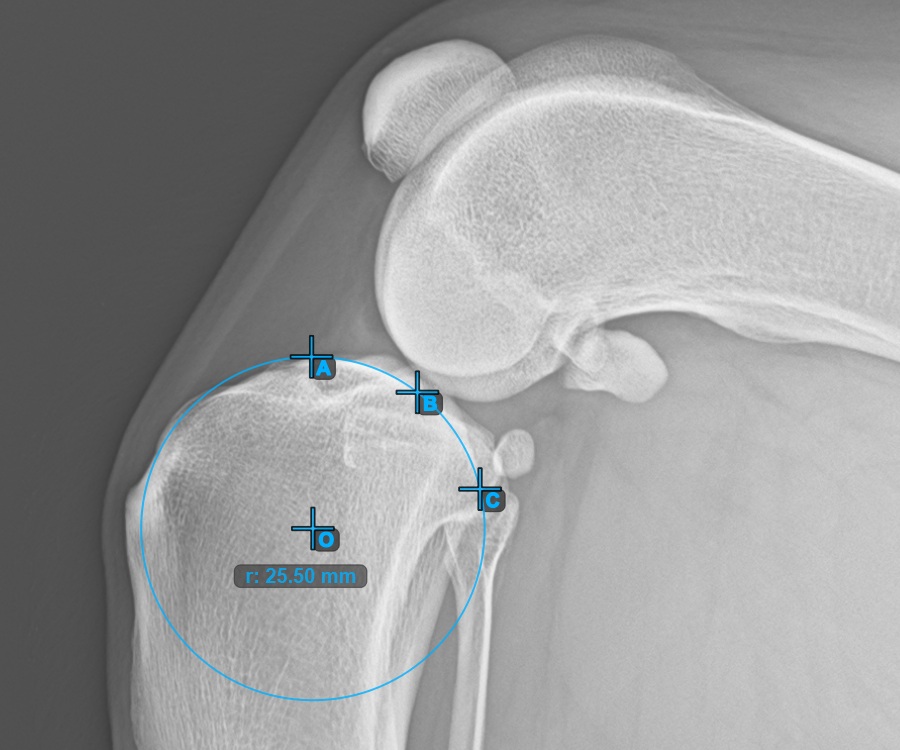

Jelölje meg a három pontot a tibia fő condylusán (Medialis Tibialis). A sorrendtől függetlenül ügyeljen arra, hogy megjelölje a legfelső pontot, a legalacsonyabb pontot és a Medialis Tibialis középpontját. A három pont alapján a rendszer automatikusan létrehoz egy kört.

A lenti kép a Condylus Medialis Tibialis-on elhelyezett három pont tipikus elhelyezkedését ábrázolja.